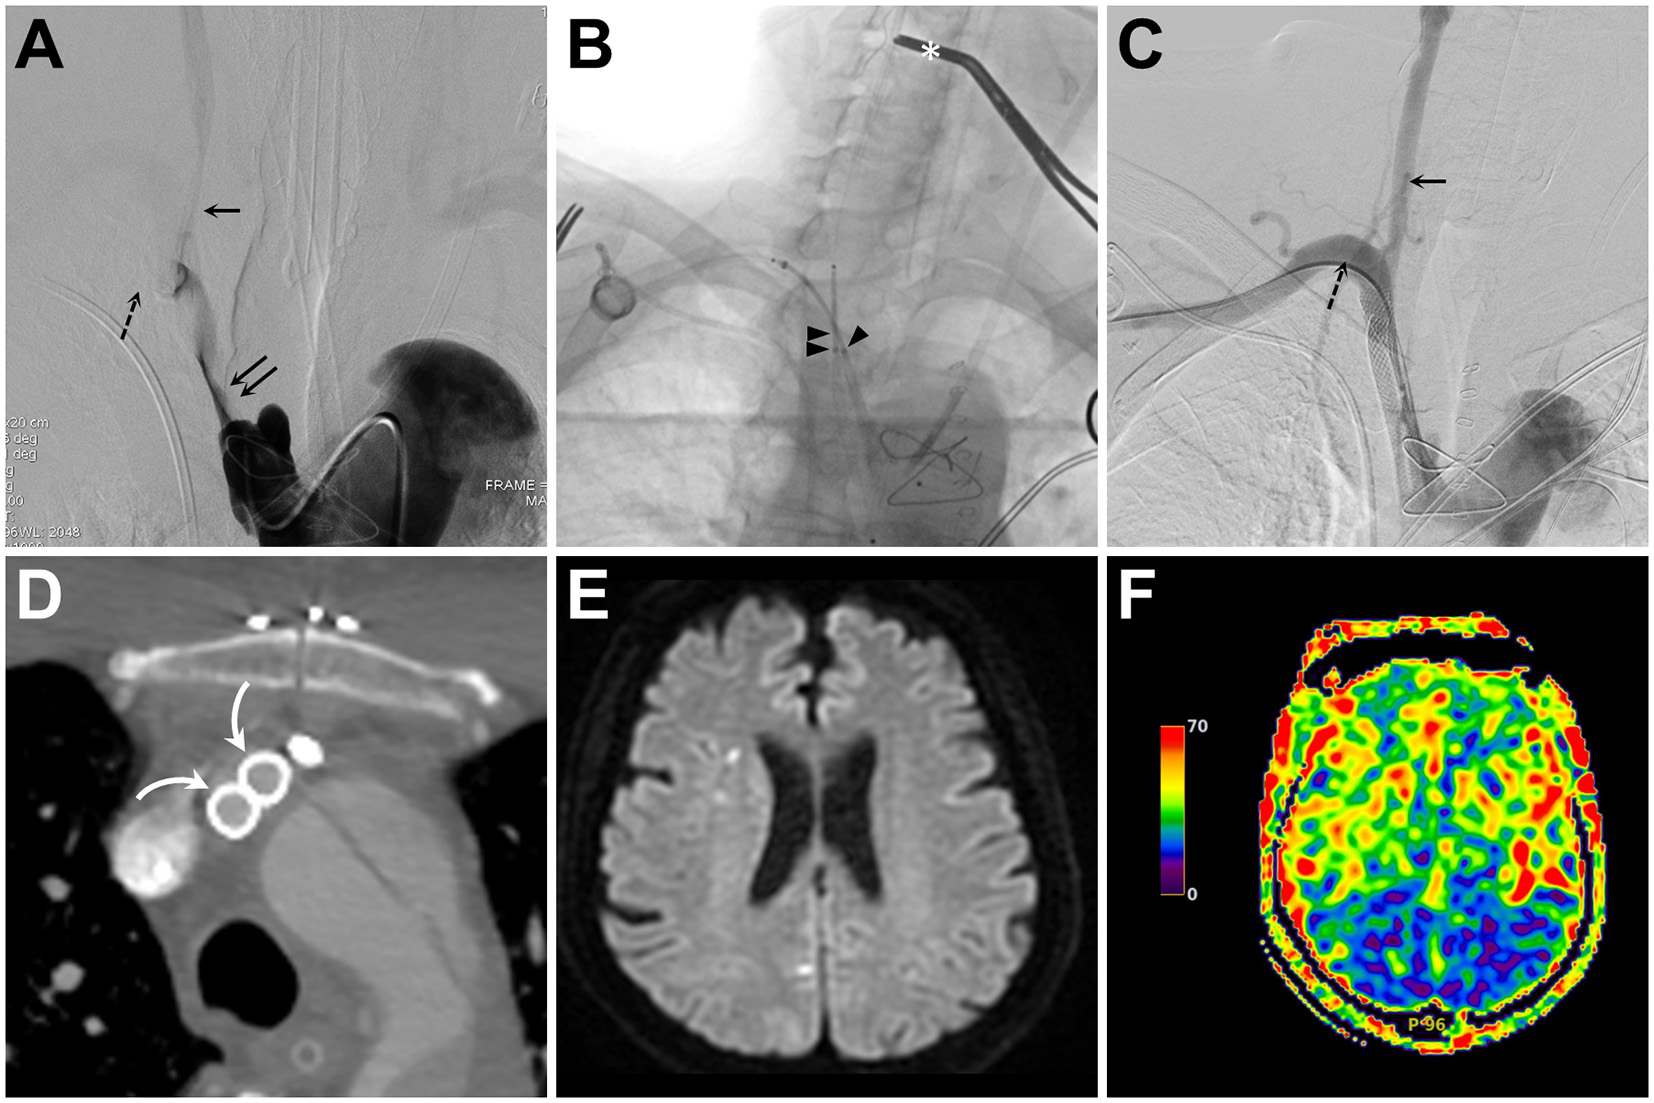

Figure 3

(A) Intra-innominate artery (IA) angiogram obtained from a transfemoral-placed angiocatheter reveals tight stenosis of the IA true lumen (double solid arrows) and compromised flow to the common carotid artery (CCA, single solid arrow) and subclavian artery (SA, single dashed arrow). (B) Fluoroscopic snapshot of the middle part of the kissing stenting procedure reveals simultaneous retrograde deployment of two Wallstents via a trans-brachial (single arrowhead) and a trans-carotid (double arrowheads) access. Also, notice the distal CCA clamp (asterisk) used for cerebral embolic protection during balloon angioplasty and stent deployment. (C, D) Following IA recanalization, both catheter angiography (C) and axial contrast-enhanced computed tomography (D) confirm good opening and apposition of both stents [curved arrow in (D)] and successful CCA (solid arrow) and SA (dashed arrow) recanalization (C). (E, F) Diffusion-weighted imaging and arterial spin labeling perfusion magnetic resonance imaging of the brain show no increase in embolic spots (E) and symmetric hemispheric perfusion (F).

The postoperative systolic blood pressure of the right upper extremity returned to normal. The patient also regained consciousness, and postoperative perfusion brain magnetic resonance imaging showed symmetric cerebral perfusion without new ischemic stroke (Figures 3E, F). The patient was treated with daily aspirin 100 mg and clopidogrel 75 mg for 3 months, followed by daily aspirin 100 mg. The patient remained neurologically intact, with a modified Rankin scale of 0, at 12 month follow-up.